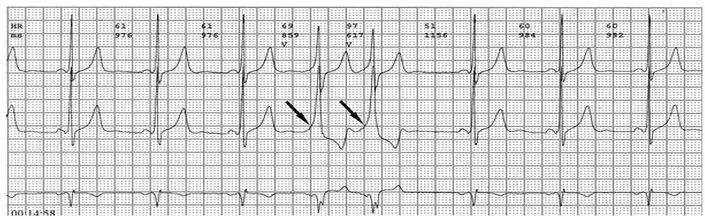

各旁路引起预激的心电图特征如下:

1、房室旁道

(1)PR间期(实质上是P-δ间期)缩短至0.12秒以下,大多为0.10秒;

(2)QRS时限延长达0.11秒以上;

(3)QRS波群起始部粗钝,与其余部分形成顿挫,即所谓预激;

(4)继发性ST-T波改变。

上述心电图改变尚有分为A、B两型的。A型的预激波和QRS波群在V1导联均向上,而B型V1导联的预激波和QRS波群的主波则均向下;前者提示左室或右室后底部心肌预激,而后者提示右室前侧壁心肌预肌。这种分类方法虽然受到预激是不同部位旁路所致的多变QRS波群的限制,但有助于区别旁路的心室端在左或右、前或后,因而沿用至今。

PR间期正常,QRS波群增宽,有预激波。预激综合征室上性心动过速发作时,预激表现大多消失,心电图表现为QRS波群形态正常的室上性心动过速。并发房扑或房颤时,QRS保持预激特征的不少见,心电图表现为QRS波群畸形宽大的房扑或房颤;心室率大多超过200次/分,甚至可达300次/分。房扑时可呈1:1房室传导,并可能辨认房扑波。房颤时心室律不规则,长间歇之后可见到个别QRS波群形态正常(可能为旁路不应期延长,房室结内隐匿传导作用消失后,冲动全部或大部经房室结传导所致),并可能辨认房颤波。心室率极快时,还可伴有频率依赖性心室内传导改变。